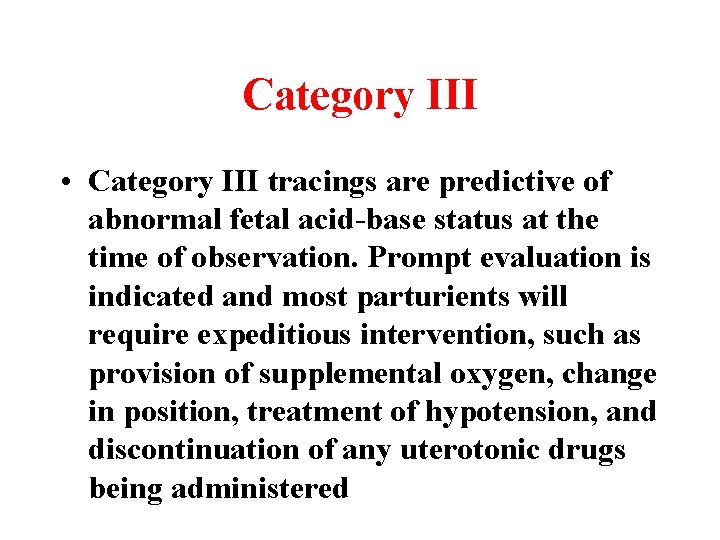

Category III • Category III tracings are predictive of abnormal fetal acid-base status at the time of observation. Prompt evaluation is indicated and most parturients will require expeditious intervention, such as provision of supplemental oxygen, change in position, treatment of hypotension, and discontinuation of any uterotonic drugs being administered